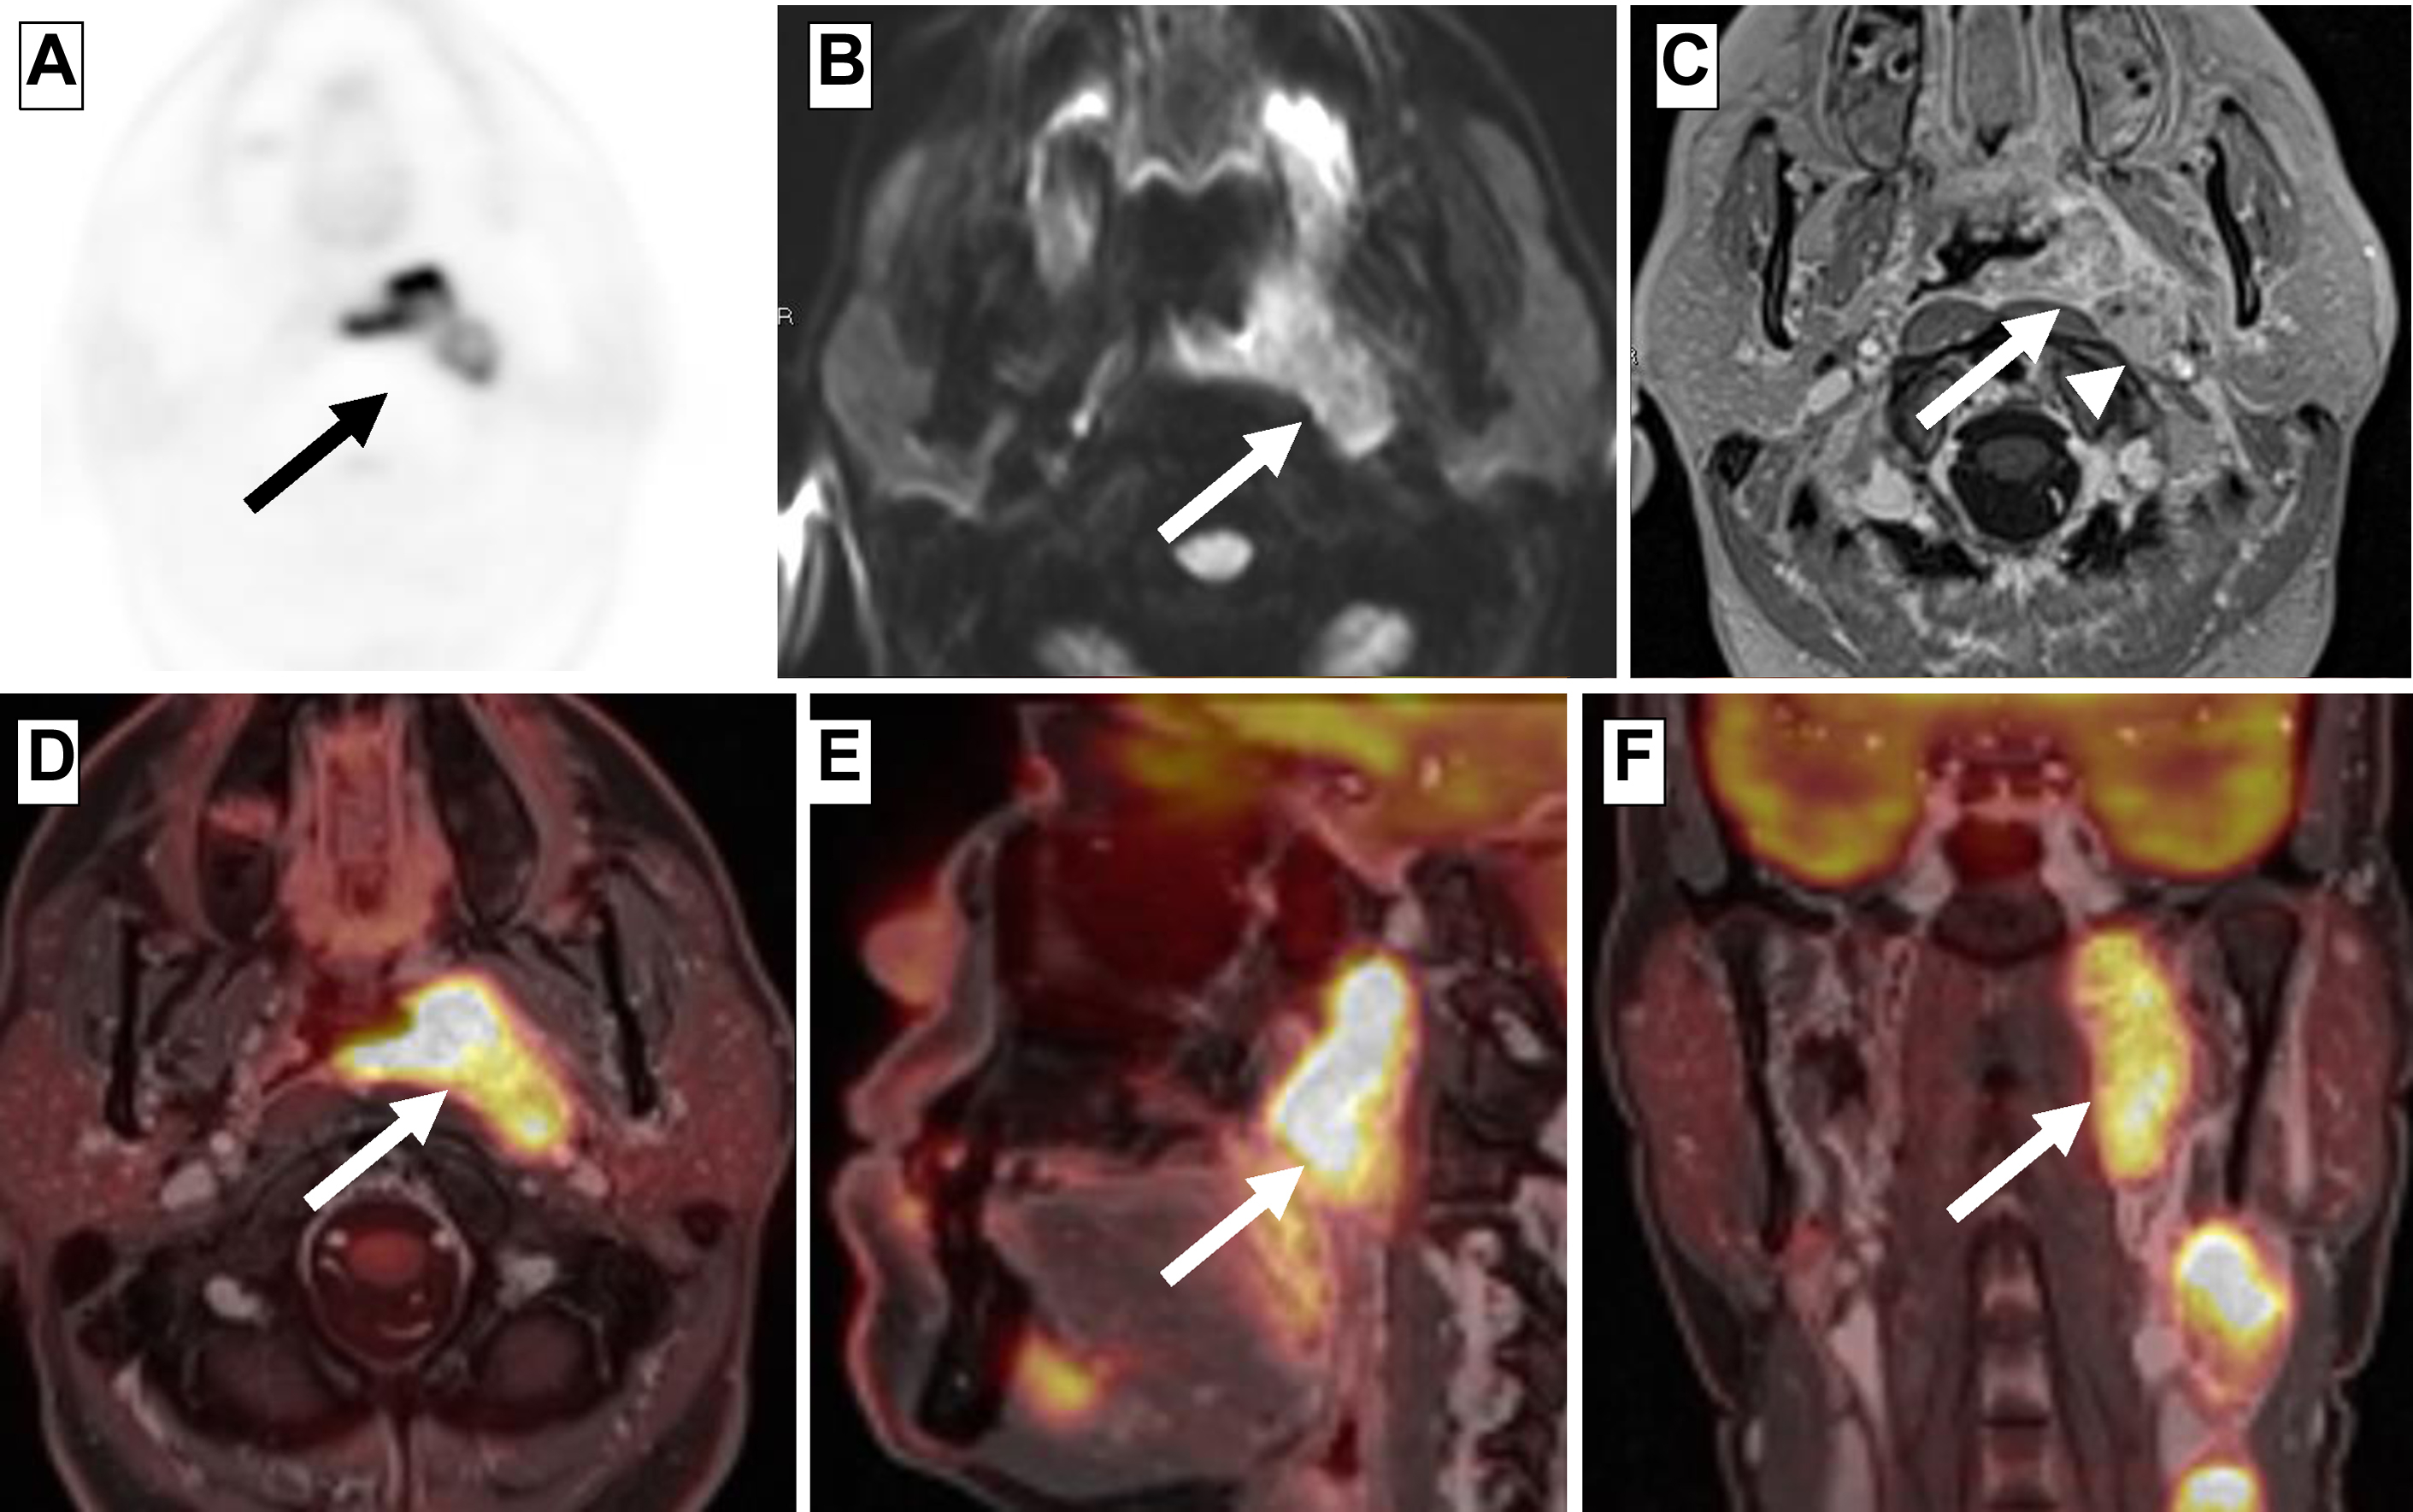

PET/CT and PET/MR Imaging of the Posttreatment Head and Neck Radiology Key

From radiologykey.com

PET/CT and PET/MR Imaging of the Posttreatment Head and Neck Radiology Key Pet The Head Pet head is the brand that helps create bounding love between you and your dog. We carry a large selection and the top brands like pet head and. Our fruity grooming ranges, fit any dog’s coat and nose which includes soothing shampoos, nourishing conditioners, hydrating sprays, soft. The test accurately details the size, shape, and function of. Natural ingredients and. Pet The Head.

PET/CT and PET/MR Imaging of the Posttreatment Head and Neck Radiology Key Pet The Head Our fruity grooming ranges, fit any dog’s coat and nose which includes soothing shampoos, nourishing conditioners, hydrating sprays, soft. A deodorising range suitable for all dogs and everyday use. Discover a wide range of premium pet head grooming products for your furry friends. Shop chewy for low prices and the best the company of animals pet head! The test accurately. Pet The Head.

PET/CT and PET/MR Imaging of the Posttreatment Head and Neck Radiology Key Pet The Head Find pet head sensitive soul dog spray deodorant for dogs with sensitive skin 10.1 fl. Pet head is the brand that helps create bounding love between you and your dog. Natural ingredients and vegan deodorizing spray. A deodorising range suitable for all dogs and everyday use. A brain positron emission tomography (pet) scan is an imaging test that allows doctors. Pet The Head.

PET/CT and PET/MR Imaging of the Posttreatment Head and Neck Radiology Key Pet The Head Natural ingredients and vegan deodorizing spray. Pet head is the brand that helps create bounding love between you and your dog. From potential injury to misunderstood signals, there are numerous factors to consider when it comes to petting a dog in the right way. We carry a large selection and the top brands like pet head and. A deodorising range. Pet The Head.